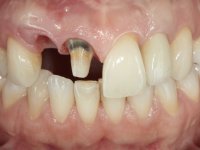

Paciente do sexo feminino, com 36 anos de idade, não fumadora. Apresentava o dente 1.1 com uma tonalidade mais escura que os dentes adjacentes. Feito o exame imagiológico, observou-se que o dente 1.1 tinha tratamento endodôntico, a paciente tinha 3 implantes colocados, dois no local dos dentes 1.2 e 2.2 e o outro no 4.6. A paciente tinha sido tratada ortodonticamente, apresentava um fenótipo gengival médio e uma boa higiene oral. Após 5 anos da primeira intervenção a paciente apresenta-se na consulta com sintomatologia infeciosa compatível com uma peri-implantite nos implantes 1.2 e 4.6. Após exame clínico, foi confirmada imagiológicamente. A perda óssea vertical tinha mais de 4mm nas duas situações.

Na primeira intervenção foi proposto à paciente uma coroa total com infraestrutura em Zr revestida por cerâmica. O facto do dente ter um tratamento endodôntico foi determinante nesta opção. Na segunda intervenção, foi proposto a remoção dos dois implantes. No implante colocado no local do dente1.2 seria feita uma regeneração óssea simultânea à colocação do novo implante. Contando com a inevitável retração gengival na zona cervical da coroa do 1.1, foi também proposto refazer a coroa do dente 1.1. Foi também adiantado que por questões de simetria, se fosse necessário, também poderia ter que se intervir no dente 2.2. Assim, na zona antero-superior, teríamos coroa aparafusada sobre um novo implante colocado no 1.2, nova coroa no1.1 e uma faceta ou coroa no dente 2.1 se necessário. No implante colocado na zona do 4.6, propomos removê-lo, colocar um novo implante, posteriormente reabilitado com uma coroa aparafusada.

Após 5 anos da primeira intervenção, a paciente surge na consulta com uma peri-implantite nos implantes colocados no local dos dentes 1.2 e 4.6. Começamos por abordar a peri-implantite no local do dente 2.2. Foi feita uma ponte provisória de laboratório em acrílico com 2 elementos. O dente 1.1 como pilar e o 1.2 como pôntico, este último apresentava um apoio distal. A coroa do 1.2 foi removida do coto com um corte longitudinal feito com turbina e depois foi fraturada com um mini luxador. O coto foi de seguida desaparafusado do implante. Fez-se o mesmo procedimento para remover a coroa do 1.1. O dente 1.1 foi re-preparado e a ponte provisória foi rebaseada em boca com acrílico autopolimerizável. Feito o correto acabamento e polimento da provisória foi feita a sua cimentação temporária com cimento de policarboxylato. Numa consulta posterior. foi feita a remoção da ponte provisória, feita a cirurgia para explantação do implante, colocou-se um novo implante e fez-se a regeneração óssea da zona com uma membrana não reabsorvível. 3 meses após foi removida a coroa do implante colocado no 4.6. Foi feito um corte horizontal com turbina na zona cervical e com um mini luxador descolou-se a coroa do coto. Após este procedimento fez-se a explantação do implante. Após 6 meses foi colocado um novo implante no local do 4.6. Após a osteointegração foi feita a impressão com a técnica de moldeira aberta e foi confecionada em laboratório uma coroa aparafusada sobre o implante. Aprovada pela paciente foi apertada definitivamente em boca. Após 1 mês removemos a ponte provisória antero-superior, reforçamos o dente 1.1 com um poste intra- radicular e reconstruimos o coto com uma resina de polimerização dual. Nessa mesma consulta expomos o implante colocado no 1.2 e fizemos uma impressão pela técnica de moldeira aberta com silicone de dupla viscosidade e presa rápida. No laboratório foi feita uma ponte provisória de 2 elementos, aparafusada sobre o implante e cimentada sobre o dente. A primeira ponte provisória foi removida e colocada a segunda aparafusada sobre o implante. A linha de acabamento cervical do 1.1 foi rebaseada com resina composta durante o aperto do parafuso do implante. Depois foi removida, foram feitos os acabamentos e finalmente apertada sobre o implante e cimentada temporariamente sobre o dente. Após 2 meses de maturação dos tecidos moles em função do perfil de emergência criado pela nova ponte provisória, pudemos avaliar a estética conseguida em conjunto com a paciente. Neste longo processo o dente 2.1 teve que fazer um tratamento endodôntico. Decidiu-se assim fazer também uma coroa no dente 2.1.O dente 2.1 foi preparado na mesma consulta em que se fez a impressão ao implante. A ponte provisória foi utilizada para individualizar a peça de transferência, copiando o seu perfil de emergência e em seguida foi realizado o afastamento gengival com caolino. A impressão foi feita com a técnica de moldeira aberta com silicone de dupla viscosidade e presa rápida. Após a escolha da cor, a impressão foi enviada  para o laboratório onde foram confecionadas 2 coroas  com infraestrutura em Zr. revestidas a cerâmica para os dentes 1.1 e 2.1 e uma coroa aparafusada sobre o implante no dente 1.2. O trabalho final foi aprovado pela paciente e foi colocado definitivamente em boca. A coroa sobre o implante foi aparafusada com 35 N e as coroas foram cimentadas com cimento de ionómero de vidro reforçado com resina.